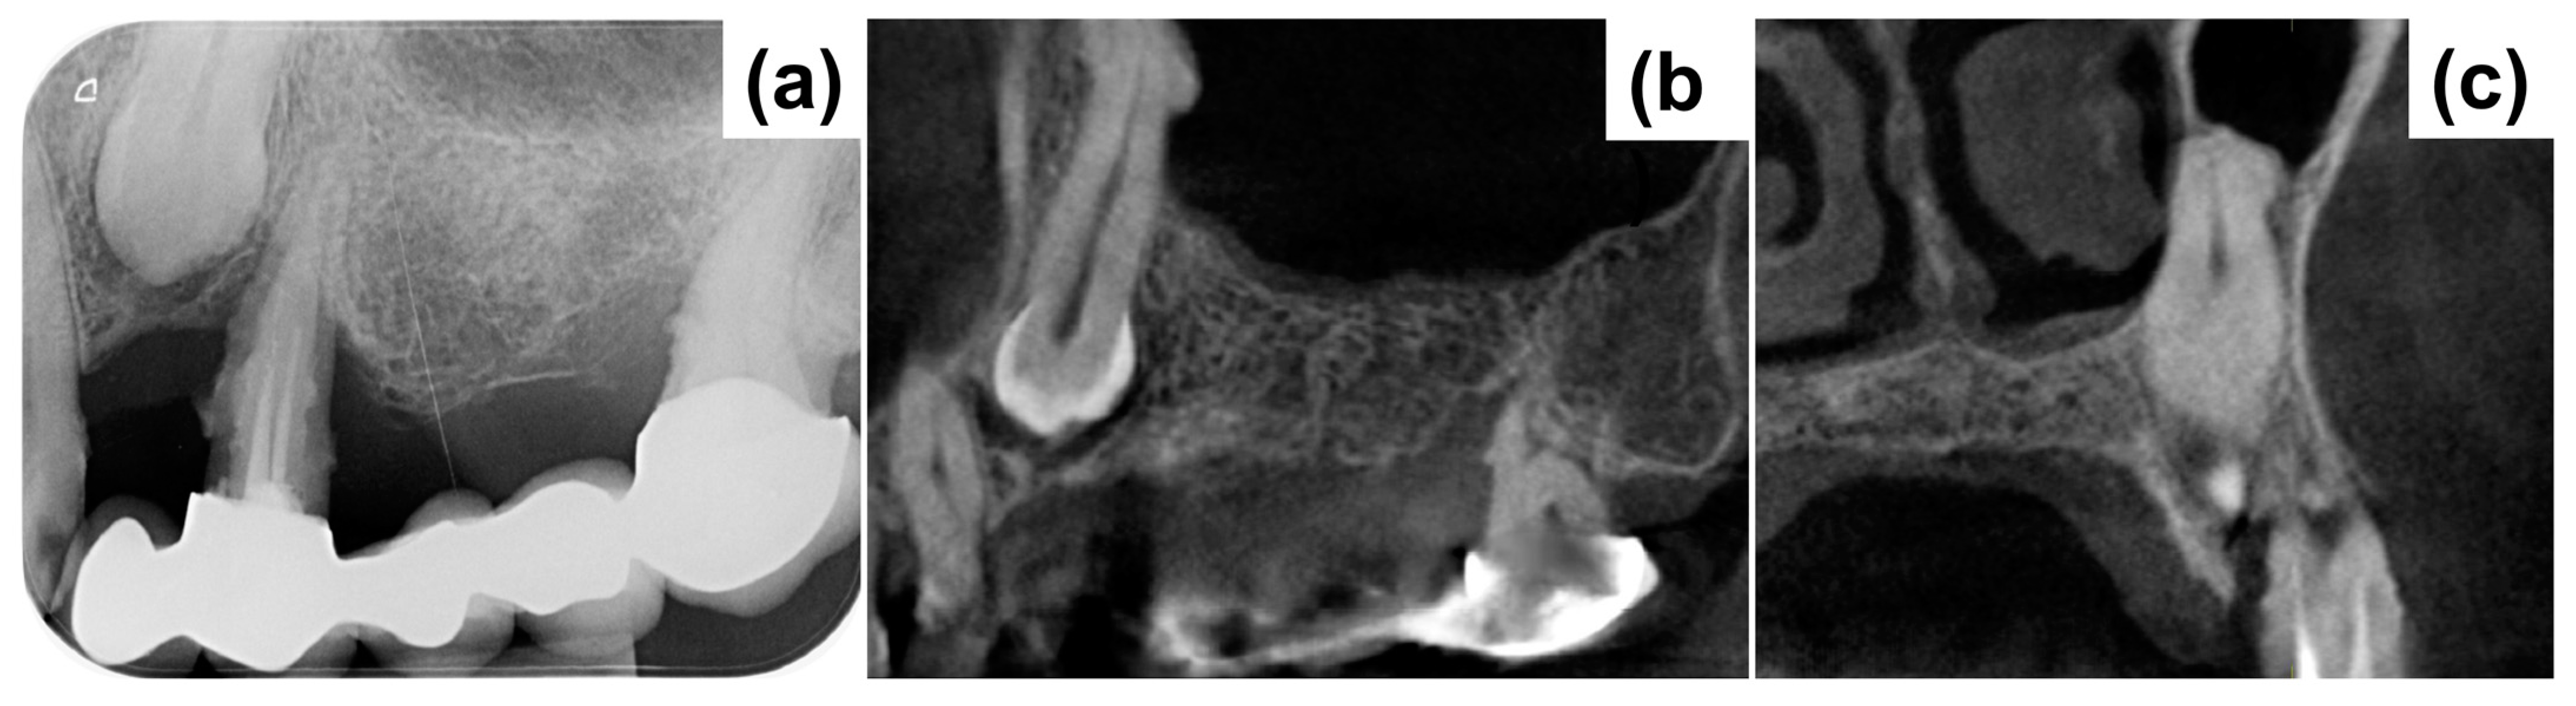

Periapical X-ray (Figure 1a) showed periapical bone loss to the first premolar (24), which appears to have been treated endodontically in an incongruous way. The second molar (27) showed a mesial bone defect. The X-ray also showed the presence of an impacted canine (23) with increased peri-coronal space, indicating a possible bacterial contamination. In order to evaluate the impacted canine and set the treatment plan, cone beam computed tomography (CBCT) was executed (Figure 1b,c). The CBCT examination highlighted an area of radiotransparency for the impacted canine and the complete loss of bone support for tooth 24. It also highlighted an alteration in the shape of the apex of the canine in contact with the maxillary sinus.

Figure 1.

(a) Initial X-ray demonstrating peripheral bone loss to the first premolar 24. (b,c) cone beam computed tomography (CBCT) demonstrating severe bone loss around 24 and the positioning of the impacted canine 23.